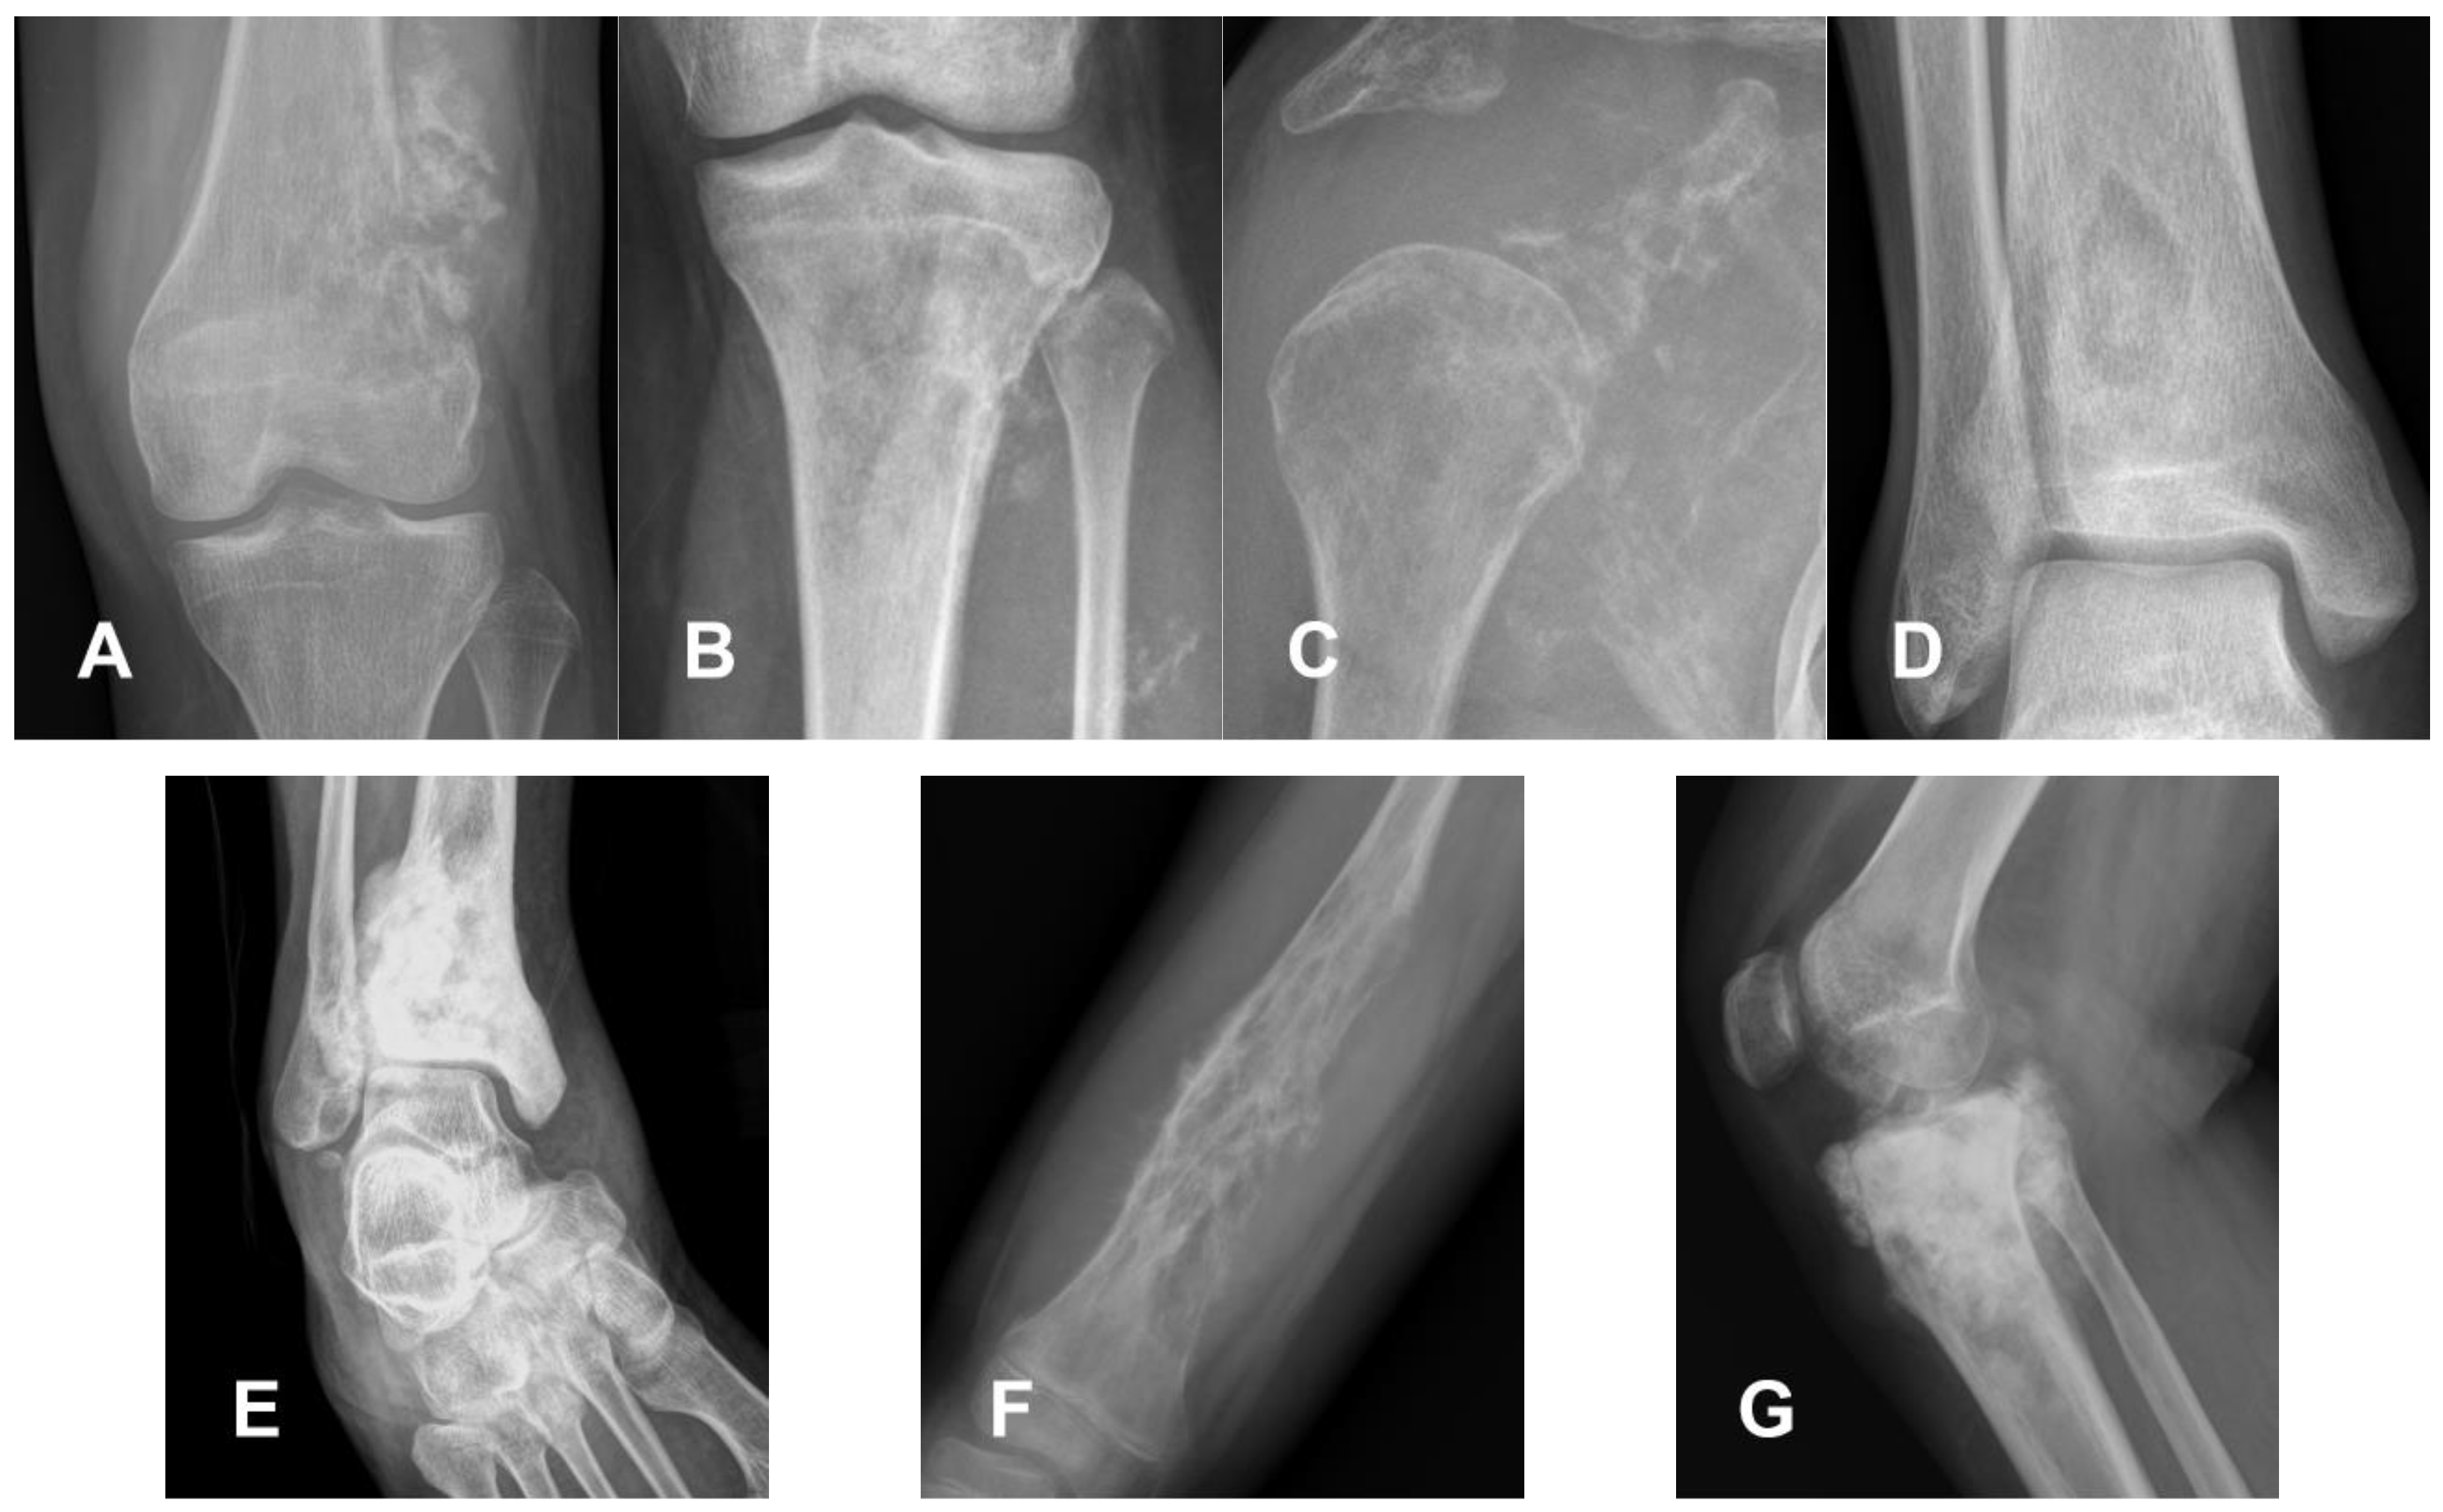

- Harper, K.; Sathiadoss, P.; Saifuddin, A.; Sheikh, A. A Review of Imaging of Surface Sarcomas of Bone. Skeletal Radiol. 2021, 50, 9–28. [Google Scholar] [CrossRef] [PubMed]

- Rose, P.S.; Dickey, I.D.; Wenger, D.E.; Unni, K.K.; Sim, F.H. Periosteal Osteosarcoma. Clin. Orthop. Relat. Res. 2006, 453, 314–317. [Google Scholar] [CrossRef]

- Jelinek, J.S.; Murphey, M.D.; Kransdorf, M.J.; Shmookler, B.M.; Malawer, M.M.; Hur, R.C. Parosteal Osteosarcoma: Value of MR Imaging and CT in the Prediction of Histologic Grade. Radiology 1996, 201, 837–842. [Google Scholar] [CrossRef] [PubMed]

- Lin, J.; Yao, L.; Mirra, J.M.; Bahk, W.J. Osteochondromalike Parosteal Osteosarcoma: A Report of Six Cases of a New Entity. Am. J. Roentgenol. 1998, 170, 1571–1577. [Google Scholar] [CrossRef][Green Version]

- Murphey, M.D.; Jelinek, J.S.; Temple, H.T.; Flemming, D.J.; Gannon, F.H. Imaging of Periosteal Osteosarcoma: Radiologic-Pathologic Comparison. Radiology 2004, 233, 129–138. [Google Scholar] [CrossRef] [PubMed]

- Okada, K.; Frassica, F.J.; Sim, F.H.; Beabout, J.W.; Bond, J.R.; Unni, K.K. Parosteal Osteosarcoma. A Clinicopathological Study. J. Bone Joint Surg. 1994, 76, 366–378. [Google Scholar] [CrossRef] [PubMed]

- Campanacci, M.; Picci, P.; Gherlinzoni, F.; Guerra, A.; Bertoni, F. Neff Parosteal Osteosarcoma. J. Bone Joint Surg. Br. 1984, 66-B, 313–321. [Google Scholar] [CrossRef] [PubMed]

- Dönmez, F.; Tüzün, U.; Başara, C.; Tunaci, M.; Bilgiç, B.; Acunaş, G. MRI Findings in Parosteal Osteosarcoma: Correlation with Histopathology. Diagn. Interv. Radiol. 2008, 14, 147–152. [Google Scholar] [PubMed]

- Bertoni, F.; Bacchini, P.; Staals, E.L.; Davidovitz, P. Dedifferentiated Parosteal Osteosarcoma: The Experience of the Rizzoli Institute. Cancer 2005, 103, 2373–2382. [Google Scholar] [CrossRef]

- Staals, E.L.; Bacchini, P.; Bertoni, F. High-grade Surface Osteosarcoma. Cancer 2008, 112, 1592–1599. [Google Scholar] [CrossRef] [PubMed]

- Revell, M.P.; Deshmukh, N.; Grimer, R.J.; Carter, S.R.; Tillman, R.M. Periosteal Osteosarcoma: A Review of 17 Cases with Mean Follow-up of 52 Months. Sarcoma 2002, 6, 123–130. [Google Scholar] [CrossRef] [PubMed]

- Vanel, D.; Picci, P.; De Paolis, M.; Mercuri, M. Radiological Study of 12 High-Grade Surface Osteosarcomas. Skeletal Radiol. 2001, 30, 667–671. [Google Scholar] [CrossRef] [PubMed]